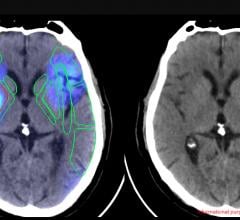

Confirma’s next-generation product for breast MRI includes a new customizable BI-RADS-centric user interface that accommodates a variety of user experience levels. Additional CADstream enhancements include improved 3D renderings and tools for morphology reporting.

The next generation of CADstream for breast MRI enhancements will include a customizable BI-RADS-centric user interface and improved volume summaries and morphology reporting tools. Additionally, the Company will debut the Access Breast Coil with high quality diagnostic capability, flexible interventional access and optimized patient comfort.